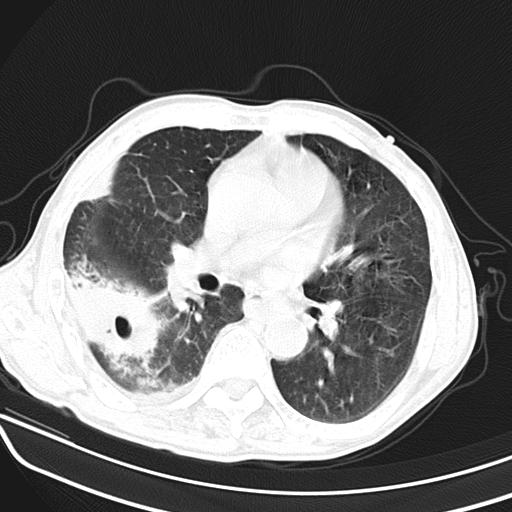

男,70,发烧咳嗽咳痰10余天,查痰结核菌阴性。否认以前有肺病史。治疗10天后症状减轻。 img]/upload/forum/2009/12/302117469692.jpg[/img]

双肺多发斑片状条索样及网格状改变,右上肺可见大个空洞,首先考虑tb慢性炎症并空洞形成。

双肺多发斑片状条索样及网格状改变,右上肺可见大个空洞,首先考虑tb慢性炎症并空洞形成。特发行纤维化。肺癌待排。

影像所见:右上肺见一巨大厚壁空洞,内壁欠光整,右上肺广泛斑片状、大片状模糊阴影。

影像所见:右上肺见一巨大厚壁空洞,并见分隔,内壁欠光整,右上肺广泛斑片状、大片状磨玻璃阴影。

这例首先确定为感染性病变应该没问题,关键是怎么解释哪个大洞的问题。结核没有卫星病灶;脓肿没有液平;病毒感染?;真菌?;寄生虫?-----?